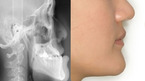

올 해 중학교에 입학한 아들을 둔 최모씨는 치아교정 때문에 고민이다. 주걱턱으로 아래 치아가 위 치아를 덮고 있는 부정교합이 심해 초등학교 4학년부터 교정을 시작한 최씨의 아들이, 턱이 계속 비뚤게 자라고 치아의 중심선도 잘 맞지 않게 되자 ‘치아교정도 소용없다’며 자주 거울을 보며 속상해 하고 있기 때문이다. 교정을 담당했던 치과에서도...